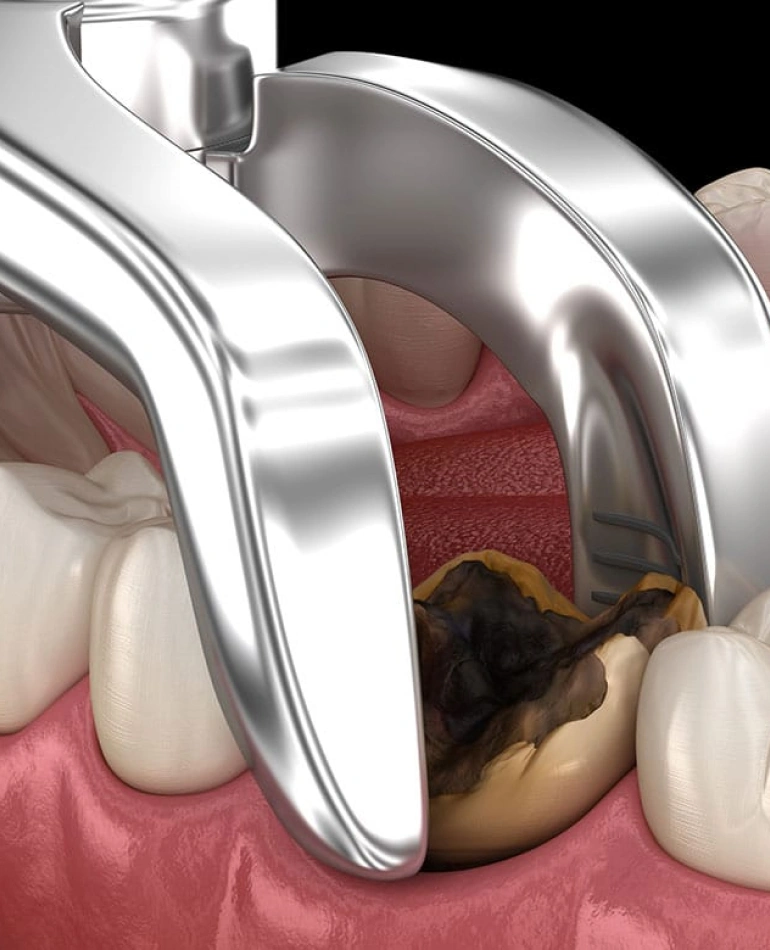

While natural teeth can frequently be preserved with prompt dental attention, there are situations where extraction may be the best course of action. If an infection or significant damage has affected the tooth's nerve, your options for treatment might be limited. In such cases, root canal therapy may provide a chance to save the tooth. However, if a tooth is so damaged that there isn’t enough structure left to support a crown, removal might be necessary to prevent further infection and to broaden your options for restorative procedures.

- Severe Decay: If a tooth is extensively decayed and cannot be restored, extraction may be necessary.

- Irreparable Damage: A tooth that is badly broken beyond repair often needs to be removed.